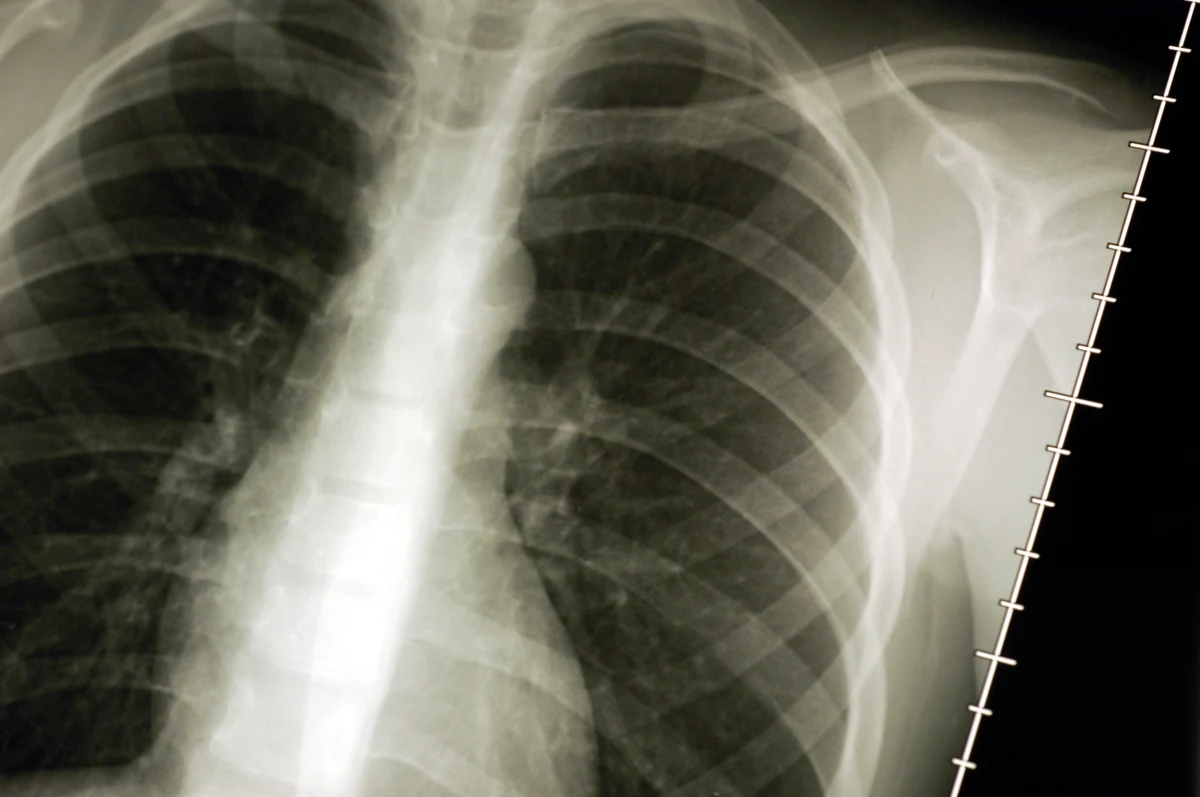

Francuscy naukowcy opracowali metodę bardzo wczesnego wykrywania raka płuc - nawet kilka lat wcześniej, zanim nowotwór będzie widoczny na zdjęciach rentgenowskich. Wszystko dzięki prostemu badaniu krwi! Pacjent dostaje ich rezultat w ciągu kilku minut.

Dzięki francuskiej metodzie znacznie zwiększona ma zostać liczba wyleczeń. Do tej pory rak płuc zazwyczaj wykrywany był bowiem bardzo często zbyt późno. Naukowcy z Nicei podkreślają jednak, ze na rozpowszechnienie tej metody trzeba będzie poczekać dwa, trzy lata. Potrzebne jest bowiem jeszcze przeprowadzenie testów klinicznych na szerszą skalę.